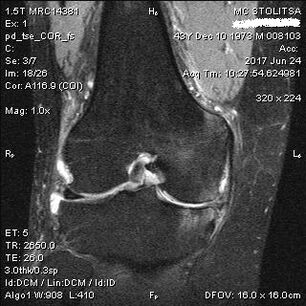

Arthrosis of the knee joint is diagnosed in the office of a rheumatologist or orthopedist.The doctor examines the affected joint, palpates it, listens to complaints and asks additional questions.Performs several tests - for example, asking the patient to bend his leg or take a few steps.Then, if it is necessary to clarify the stage of the disease or the nature of pathological changes, he will refer you for additional studies.For example, for computed tomography or radiography.